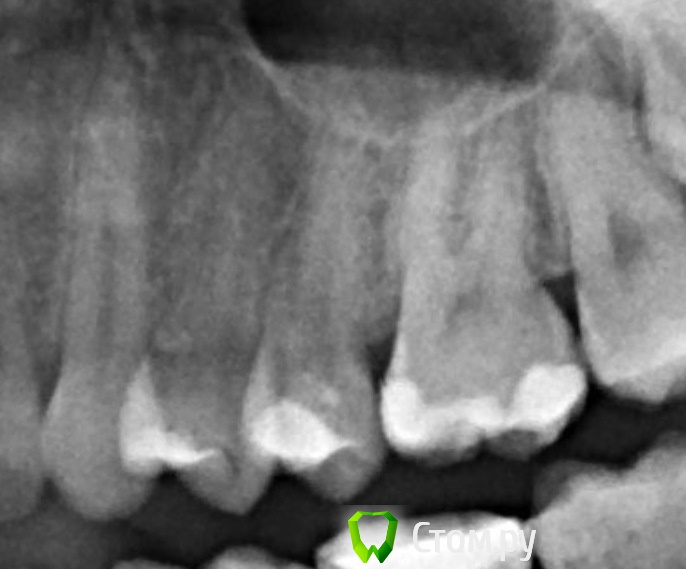

felicidade Опубликовано 18 июня, 2014 Поделиться Опубликовано 18 июня, 2014 Добрый вечер! Сегодня утром мне мой словенский стоматолог запломбировал канал 25-ого зуба. Я, конечно, не стоматолог, но мне кажется, что у меня теперь из корня выглядывают обломок файла и гуттаперча :-( Уважаемые специалисты, скажите, пожалуйста, правильно ли была проведена пломбировка канала? И если нет, то как это можно исправить? Прилагаю снимок зуба до и после пломбировки (17 и 18 июня, соответственно). Спасибо большущее заранее! Ссылка на комментарий

sydnik Опубликовано 18 июня, 2014 Поделиться Опубликовано 18 июня, 2014 Добрый вечер!ничего страшного ,незначительное выведение пломбировочного материла.а сколько каналов доктор запломбировал, не говорил? Ссылка на комментарий

faity Опубликовано 19 июня, 2014 Поделиться Опубликовано 19 июня, 2014 Добрый вечер! ничего страшного ,незначительное выведение пломбировочного материла. а сколько каналов доктор запломбировал, не говорил? верхушки 2 штуки, за обе вышли, ты из-за облачков про канал спросил? felicidade вам нужно сделать снимок в другой проекции, как бы сбоку, и естественно выложить его нам) Ссылка на комментарий

sydnik Опубликовано 19 июня, 2014 Поделиться Опубликовано 19 июня, 2014 (изменено) faity ты из-за облачков про канал спросил?да, насторожили Изменено 19 июня, 2014 пользователем sydnik Ссылка на комментарий